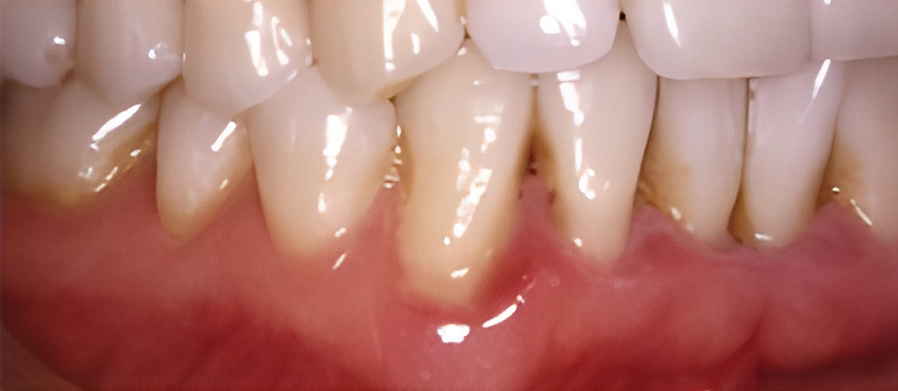

치은염을 치료하지 않고 방치하면 플라그가 뿌리로 퍼져 뼈와 연조직에 감염과 손상을 일으킬 수 있습니다. 잇몸이 치아에서 분리되어 물러나기 시작할 수 있으며 잇몸 라인 아래에 주머니가 생겨 플라크와 음식물이 쌓일 수 있습니다.

치주염은 스케일링을 통해 플라그와 치석을 제거하여 치료합니다. 문제가 되는 치주낭 부분을 제거하여 건강한 조직이 치아에 붙을 수 있도록 합니다.

잇몸이 심하게 붓고 피가 자주 나며 치가가 흔들리기도 합니다. 치아 뿌리가 드러나기도 하며 때로는 잇몸에 고름이 나와 음식물을 잘 씹을 수가 없습니다.